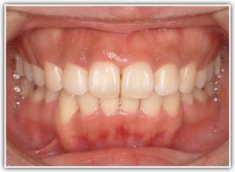

上顎前突ケース

治療法:表の矯正(T21ブラケット)

治療後(2年後)